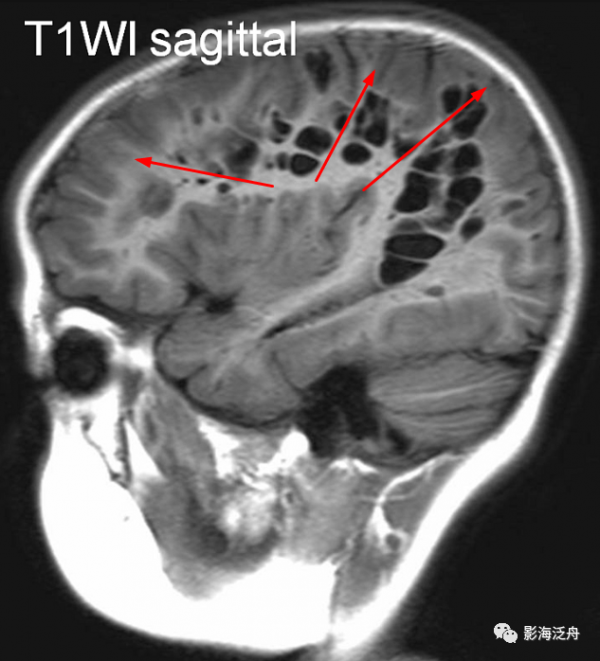

病例一:青少年男性,頭痛就診。右側大腦半球多發擴大VR腔隙,病灶沿髓質動脈走行區域(紅箭)呈簇狀分佈,VR腔隙呈類圓形或類橢圓形,邊緣光滑,灶周不伴水腫。大腦半球型擴大VR腔隙多兩側不對稱,這與基底節型不同。

![]()